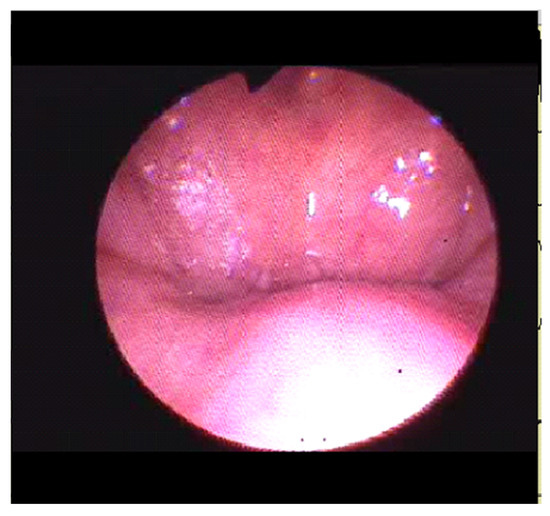

The two patients successfully underwent DISE. The procedure was performed in the operating room under the presence of an anesthesiologist, otolaryngologist, orthodontic specialist and neurophysiopathology technician. The two patients received sedation with the administration of increasing doses of propofol (3 mg/kg/h). The mean duration of the procedure was 15+/−3 min. They already prepared for polysomnography intraoperative recording, and sedation was under continuous monitoring through bispectral index (BIS) monitoring (Apect Medical Systems, Newton, MA, USA) with mean values between 50 and 70. Then, a flexible nasopharyngoscope, into the nasal cavity of 3.4 mm in diameter, was introduced to visualize and record the pattern and degree of obstruction (nasopharynx, oropharynx, hypopharynx and larynx). During DISE, in the female patient, we observed a 100% concentric retropalatal obstruction site and 75% anteroposterior epiglottis prolapsed laryngeal obstruction site (Figure 3).

Figure 3. Image of patient 1 showing obstructive apnea.